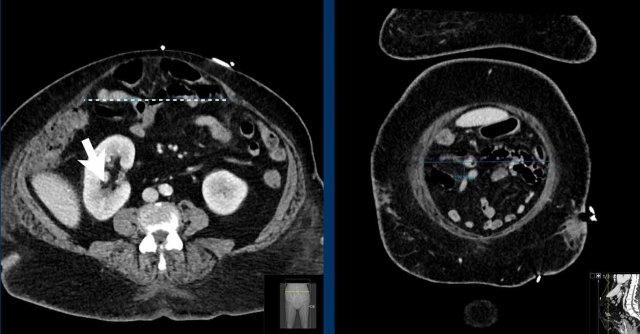

Tỷ lệ Cơ thẳng bụng trên Khuyết tật (RDR)

Tỷ lệ Cơ thẳng bụng trên Khuyết tật (RDR) là tỷ số giữa tổng chiều rộng của cơ thẳng bụng trái và phải so với chiều rộng của thoát vị.

Một tên gọi khác của chỉ số này, thường được các phẫu thuật viên sử dụng, là chỉ số Carbonell, được đặt theo tên Giáo sư Alfredo Carbonell – người đầu tiên công bố chỉ số này.

RDR là một công cụ thực tiễn và đáng tin cậy để dự đoán khả năng đóng khuyết tật thành bụng trong quá trình phẫu thuật sửa chữa thoát vị thông thường mà không cần thực hiện thêm kỹ thuật tách thành phần (CST).

Kỹ thuật tách thành phần là một kỹ thuật phẫu thuật trong đó một trong ba cơ thành bụng bên được cắt tách khỏi các cơ còn lại.

Các kỹ thuật này giúp “nới lỏng” phần thành bụng còn lại, nhưng có liên quan đến nguy cơ biến chứng hậu phẫu cao hơn (xem phần điều trị).

Nếu RDR > 2, phẫu thuật sửa chữa thông thường có thể đóng được khuyết tật thành bụng trong 90% trường hợp.

Nếu RDR < 1,5, trong hơn 52% các ca phẫu thuật, cần phải thực hiện thêm kỹ thuật tách thành phần bổ sung.

Hình ảnh

Ở bệnh nhân này, Tỷ lệ Cơ thẳng bụng trên Khuyết tật: (49 mm + 43 mm) / 157 mm = 0,58.

Tỷ lệ này dự đoán rằng việc đóng thoát vị có thể sẽ không thực hiện được nếu không tiến hành kỹ thuật tách thành phần.